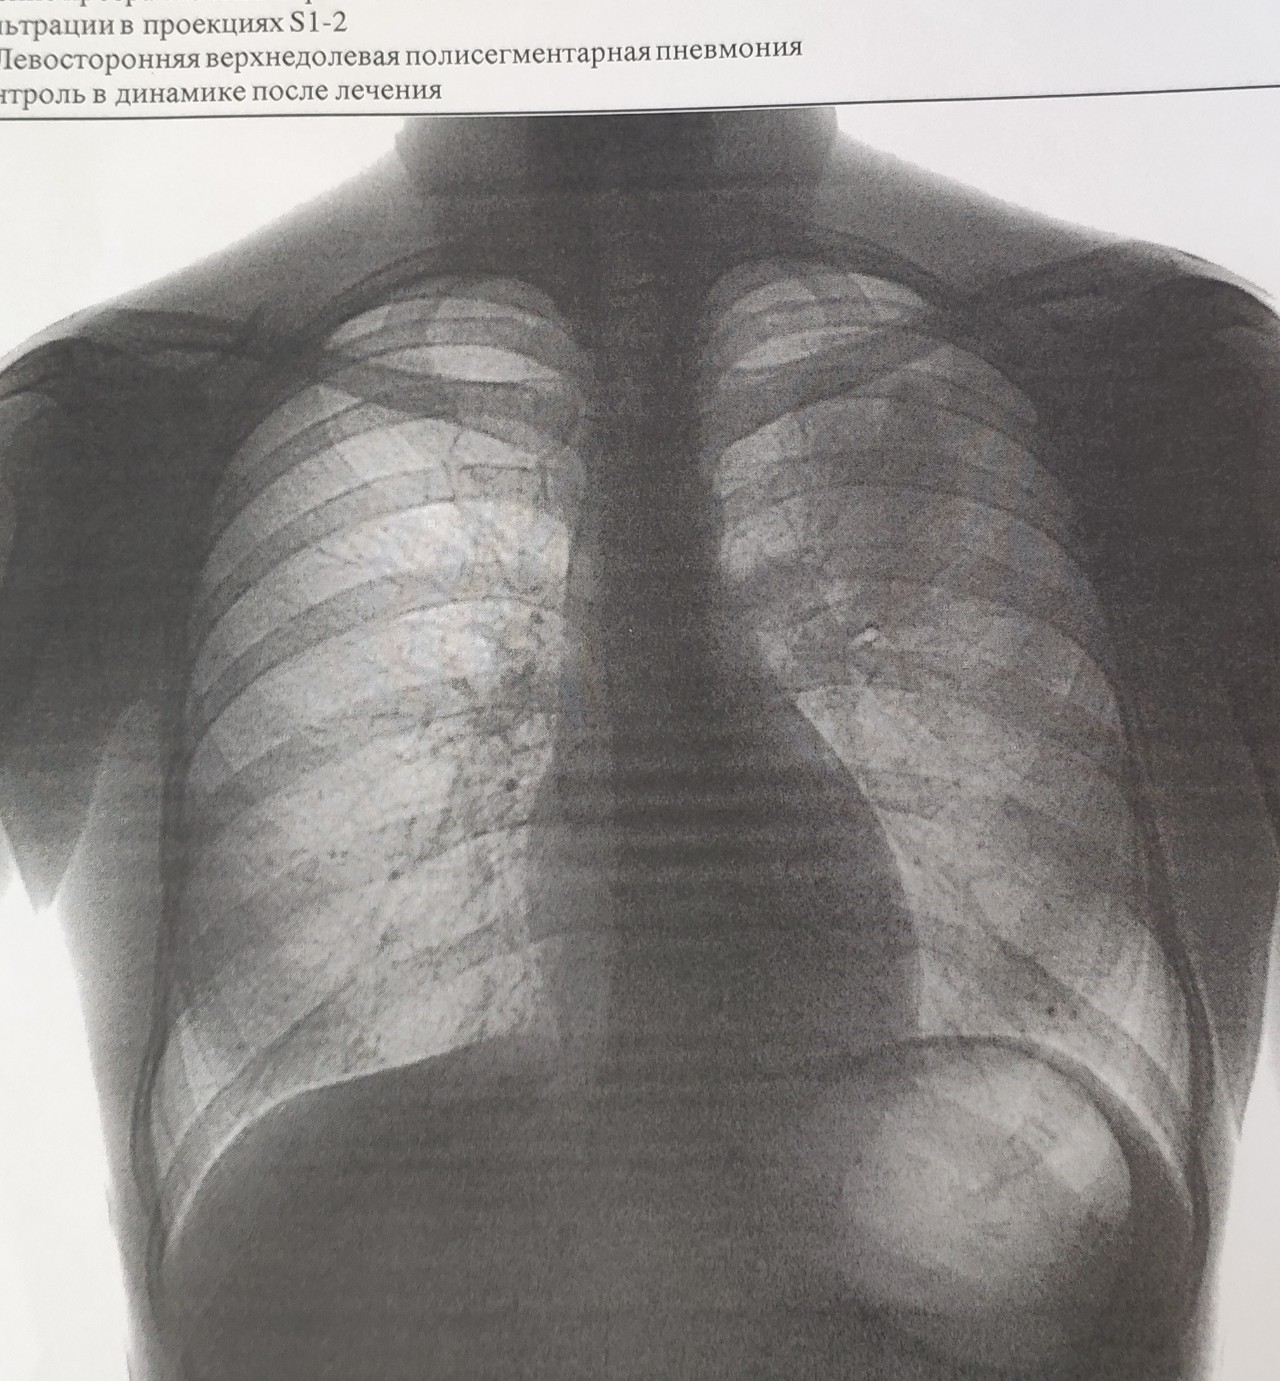

Нормальная рентгенограмма легких: что нужно знать